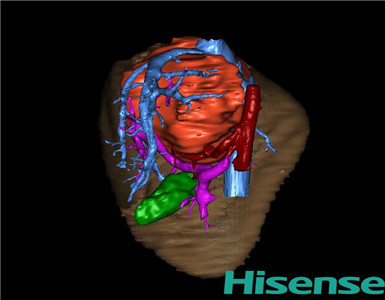

CT结果输入海信CAS系统后行3D重建及手术规划后,于2015-1-8全麻下行“肝脏肿瘤切除术”。

术前三维重建及手术方案设计:

将0.625mm双源薄层CT资料的静脉期和动脉期Dicom格式文件导入海信CAS系统。

通过调节窗宽窗位调整CT序号,对肝实质,胆囊,下腔静脉,肿瘤,肝动脉、门静脉及肝静脉等进行三维重建;系统自动计算肝脏体积。

术前三维重建:

重建图片